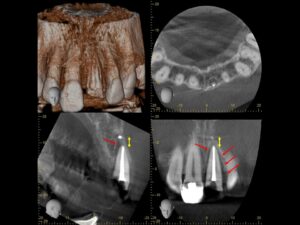

初診時レントゲンおよびCT画像。右側中切歯(向かって右)は歯髄に近接した白い充填物を認める。根管治療後、補綴治療を行うこととした。左側中切歯(向かって右)は歯槽骨にまで及ぶ歯根破折を認め(黄⇒)、通常であれば矯正的挺出あるいは抜歯のケース。過蓋咬合で矯正的挺出が行えない為、根管治療を行った上で外科的挺出を図り歯牙を保存することとした。